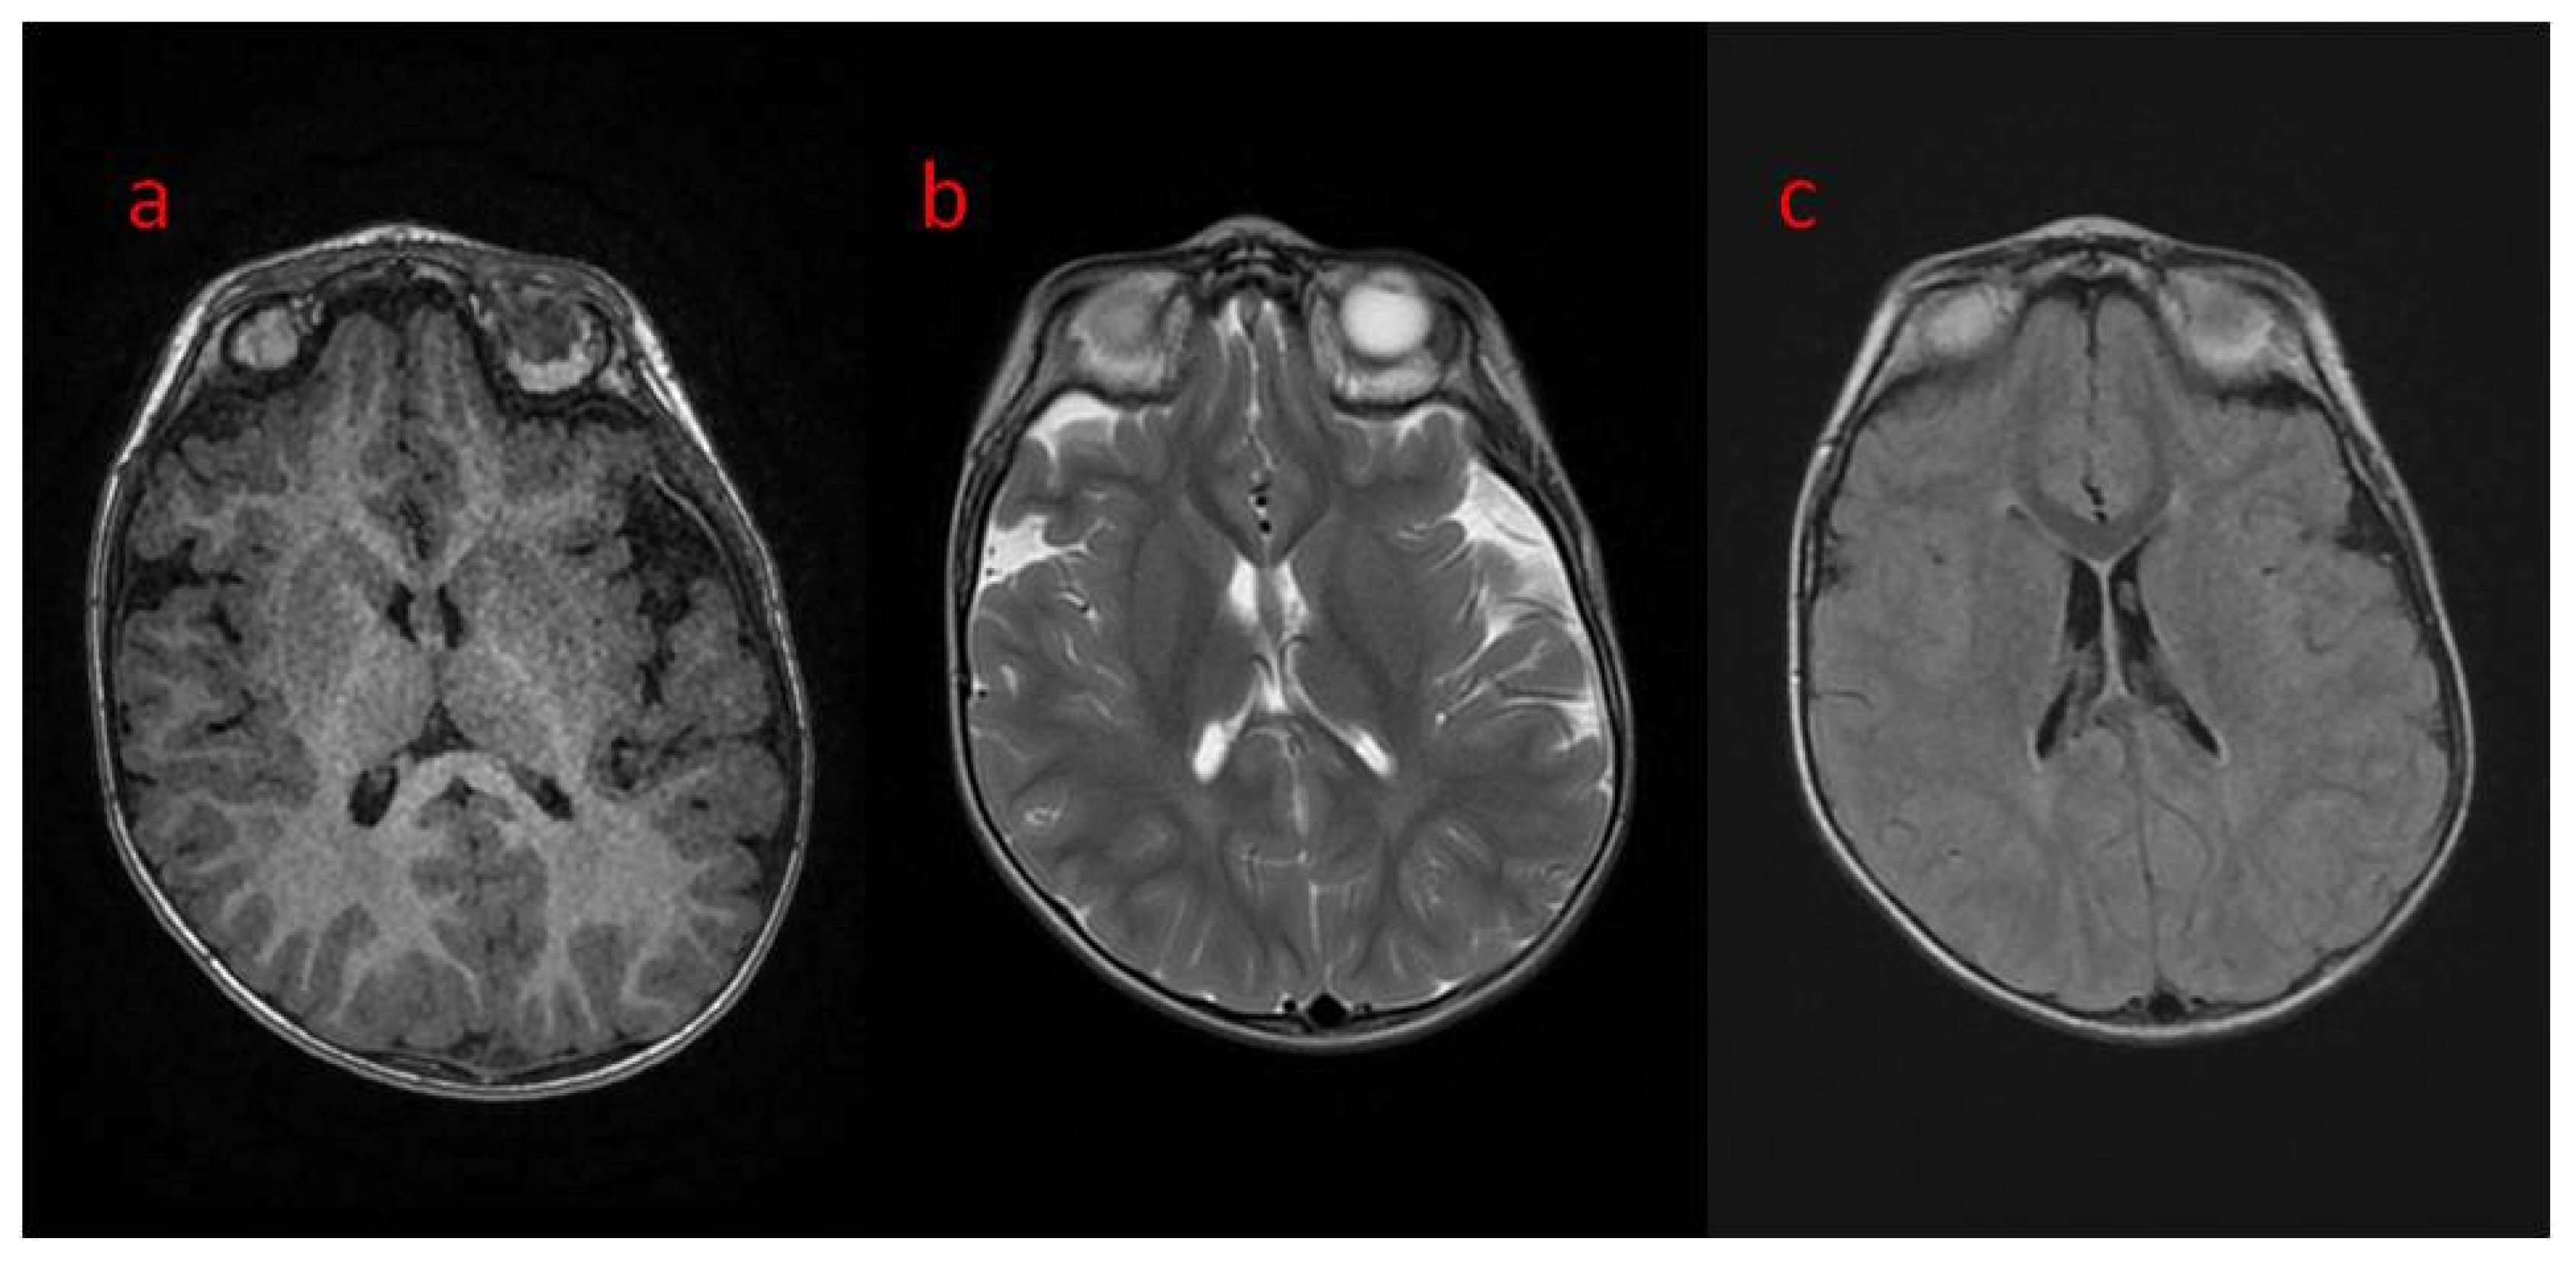

| 16 The present study | Areas of incomplete myelination (in the area of the triangles of the lateral ventricles and around the occipital horns) | Cortical visual impairment, poor eye contact, with movement disorder | Hypotonia, joint contractures | Severe global developmental delay | Dysphagia (only liquid food) | Difficult to treat, ASM resistance (valproic acid, topiramate, vigabatrin, phenobarbital, levetiracetam, phenytoin, clobazam, clonazepam, nitrazepam, lamotrigine, carbamazepine, and zonisamide), steroid therapy (adrenocorticotropic hormone, methylprednisolone—break), vagal nerve stimulation, ketogenic diet intolerance (due to reluctance to drink) |